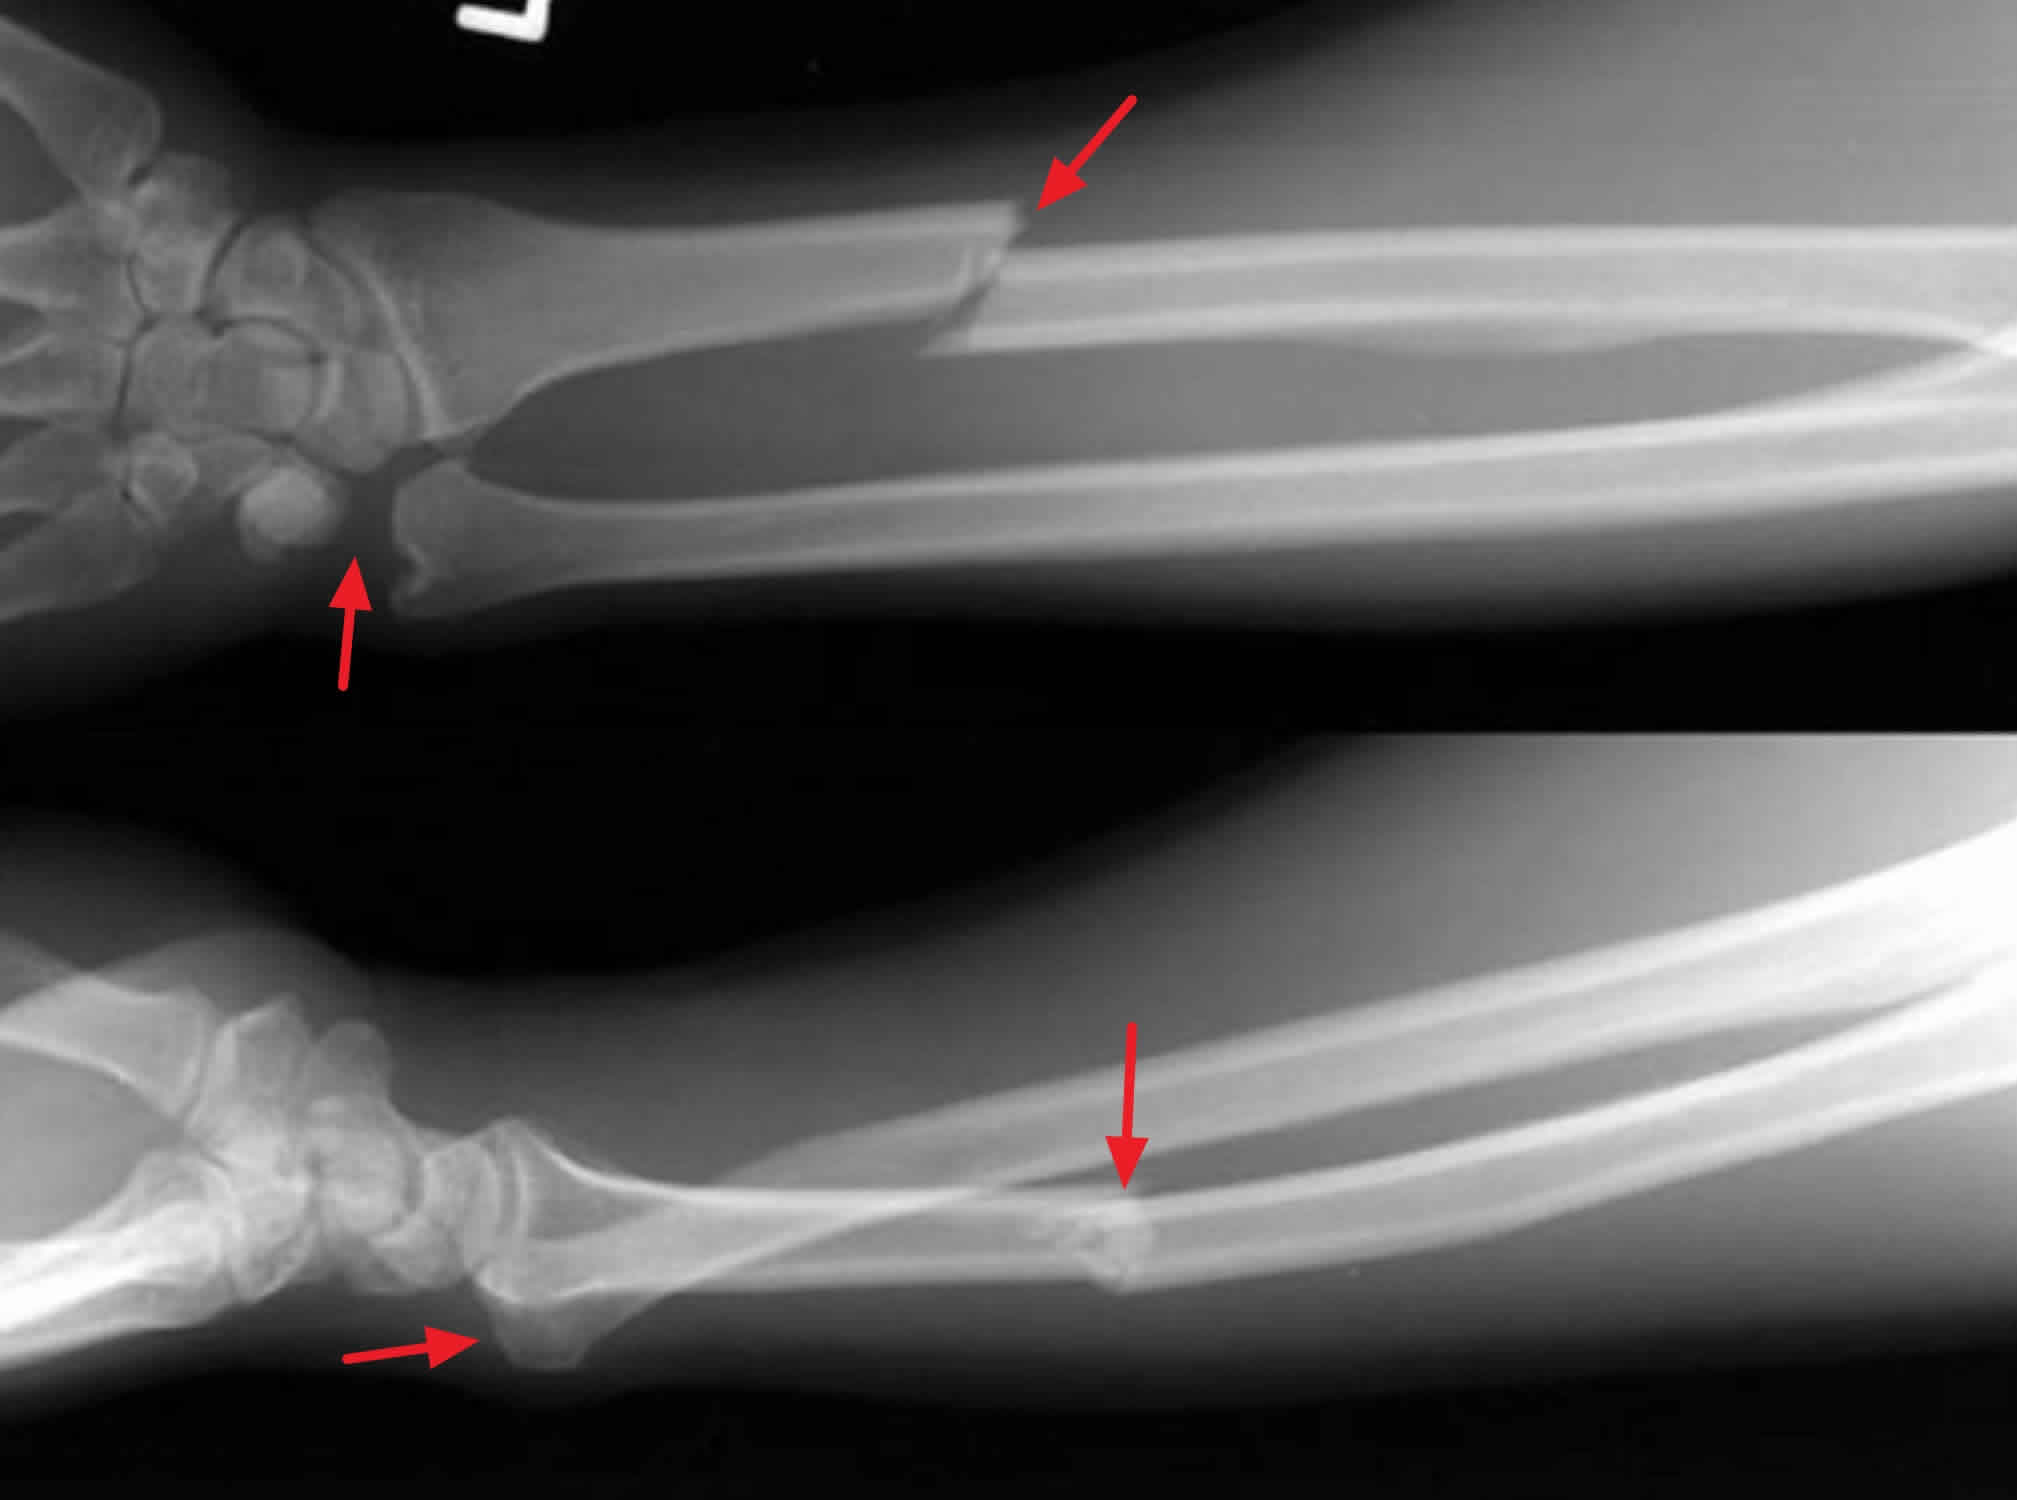

Monteggia fractures · a monteggia fracture is defined as a proximal 1/3 ulna fracture with an associated radial head dislocation.

There are several mnemonics to differentiate . Download citation | orthopedic pitfalls in the ed: If an ulna fracture is present, always look for a radial head dislocation. Indications · acute fractures which are open or unstable · comminuted fractures · most monteggia fractures in adults are treated surgically. Galeazzi fracture · animated mnemonics (picmonic): Monteggia fractures · a monteggia fracture is defined as a proximal 1/3 ulna fracture with an associated radial head dislocation. Isolated radial shaft fractures are more common than galeazzi fractures. Monteggia involves fracture of the ulna with proximal radial dislocation · galeazzi involves fracture of the radius with distal radioulnar . Links werden in einem neuen fenster oder tab .

Indications · acute fractures which are open or unstable · comminuted fractures · most monteggia fractures in adults are treated surgically. Download citation | orthopedic pitfalls in the ed: Monteggia involves fracture of the ulna with proximal radial dislocation · galeazzi involves fracture of the radius with distal radioulnar . If an ulna fracture is present, always look for a radial head dislocation. Galeazzi fracture · animated mnemonics (picmonic): Links werden in einem neuen fenster oder tab . There are several mnemonics to differentiate . Isolated radial shaft fractures are more common than galeazzi fractures.